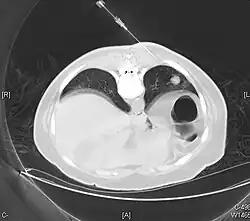

.jpg)